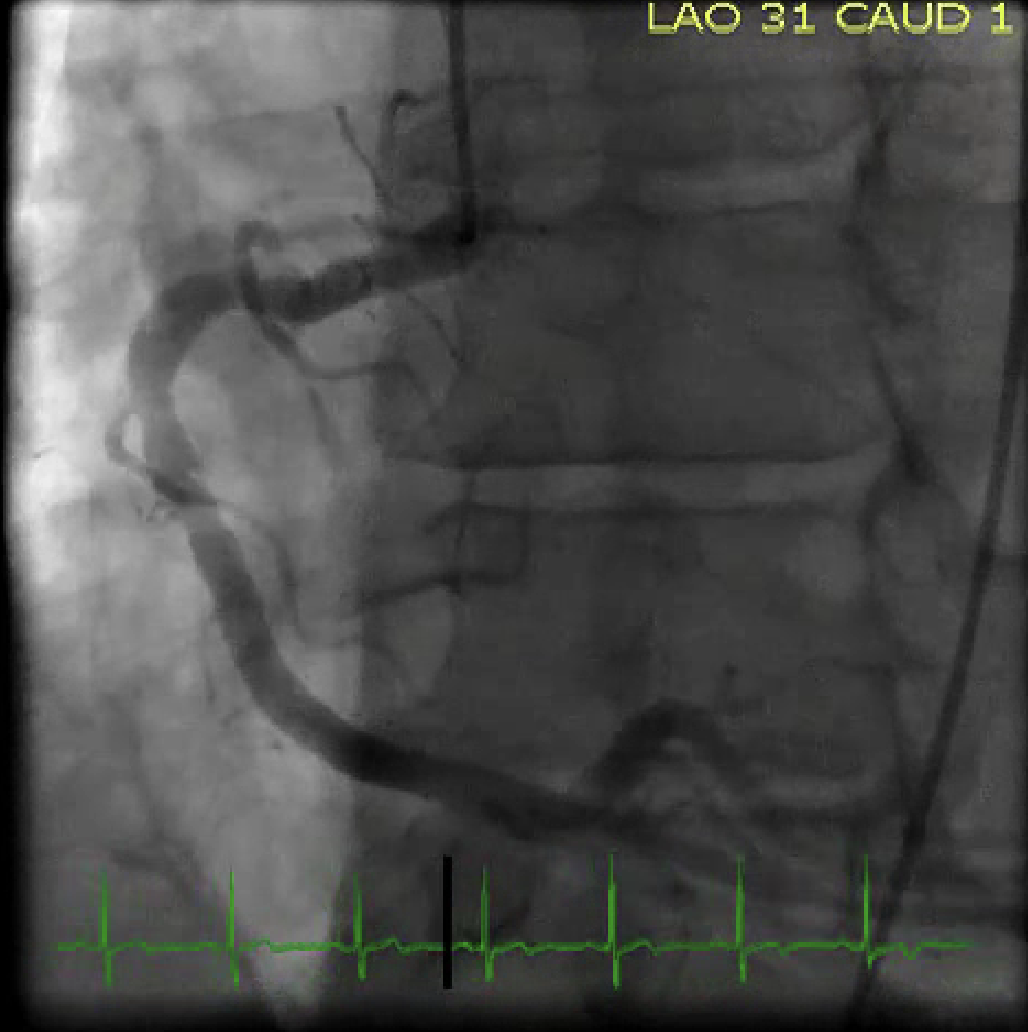

Describe the findings